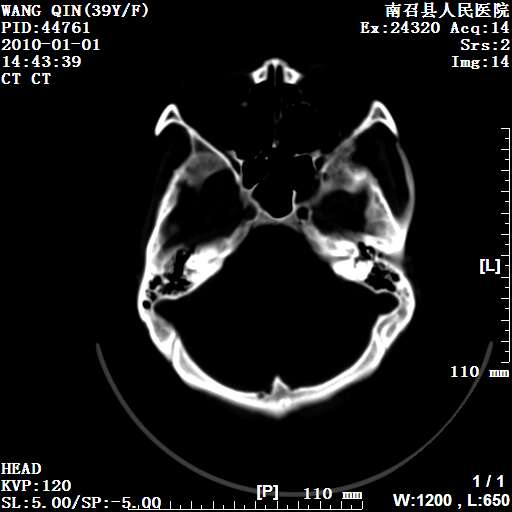

以下是引用随光逐影在2010-1-22 9:03:00的发言:[br]考虑左侧中颅窝(蝶骨翼区)脑膜瘤侵犯蝶骨翼并突入左侧眼眶。

以下是引用水过无痕在2010-1-22 14:55:00的发言:[br]一、定位:颅外占位;二、定性:恶性可能性大;三、组织来源:来源于左侧眼外直肌或其他部位;考虑为:横纹肌肉瘤>转移瘤>脑膜瘤.